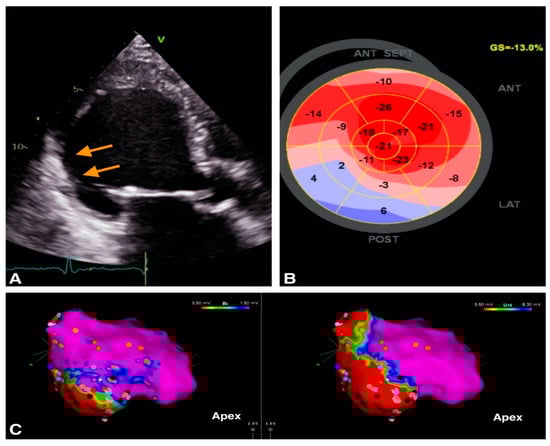

2. Role of Echocardiography in Identification of VA Substrate

2.1. VA in Structural Heart Disease